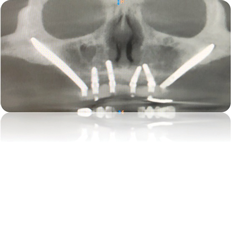

Treatment options for full-arch restorations include the placement of conventional implants in the anterior region accompanied by single zygomatic implants in the posterior left and right (Figure 1),48 the classic "quad zygoma" concept with four zygomatic implants in position (Figure 2),19,49 and the pterygoid fixated arch stabilization technique, which combines two anterior conventional implants, two zygomatic implants, and two pterygoid implants (Figure 3).50 Treatment plans can now be customized to optimize the implant positions based on each patient's anatomy and needs.

(1.) Radiograph of zygomatic implants added to a group of anterior conventional implants.

Figure 1